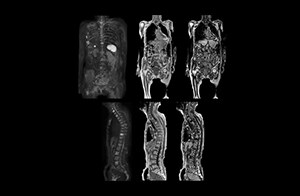

“When we limited the scan coverage to the area from neck to femur, we could fit more clinical information in approximately the same scan time. So, we added coronal mDIXON, sagittal T1-weighted, and sagittal STIR sequences to our examination, instead of performing only axial DWIBS and coronal single-shot TSE scans.” The single shot T2-weighted TSE images are used for morphology and compared to DWIBS images to identify T2 shine-through. Sagittal STIR images are used in patients with inflammation or bone metastasis.

“Switching to coronal DWIBS – rather than axial – further shortens scan time,” says Mr. Naka. “Important is that a dS SENSE factor of 5 shortens exam time while high image quality can be maintained, thanks to Ingenia’s dStream architecture.” He adds that the coronal orientation also avoids artifacts that are specific to combining axial images.

“When we use a coronal DWIBS acquisition, we can perform a full whole body examination, including other required sequences, within 30 minutes,” he says.